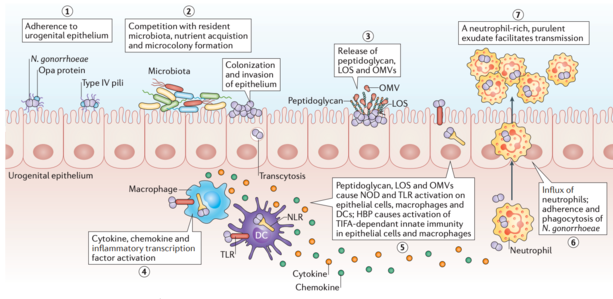

Course Path4172019w2 Case 2 Ubc Wiki

Course Path4172019w2 Case 2 Ubc Wiki